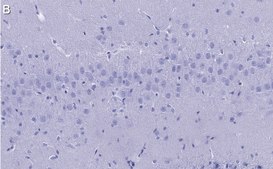

Immunohistochemistry (Paraffin) Analysis: A 1:100 dilution from a representative lot detected Synaptophysin in rat brain tissue sections.